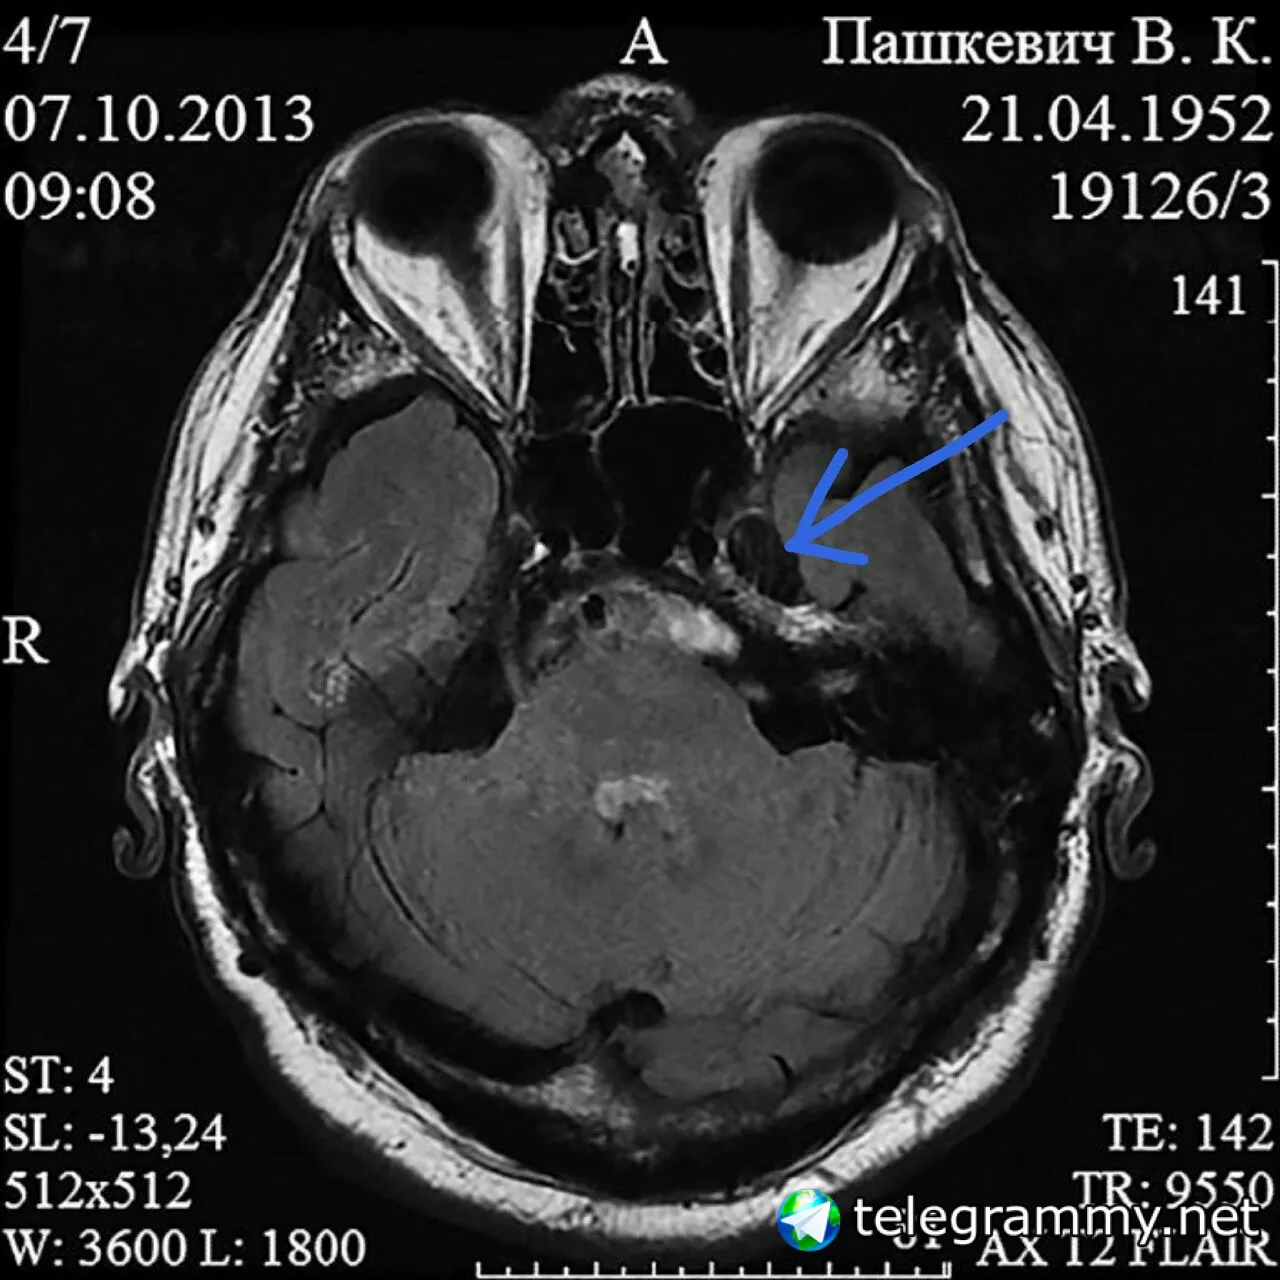

Случай атипичного течения демиелинизирующего заболевания ЦНС Демиелинизирующие заболевания центральной нервной системы (ЦНС) – обширная неоднородная группа заболеваний с различными этиопатогенетическими механизмами и преимущественным поражением белого вещества головного и/или спинного мозга. Одной из особенностей демиелинизирующих заболеваний ЦНС является то, что диагностика их часто является рутинной, не выходящей за рамки принятых диагностических схем. Однако возможный широкий спектр клинических симптомов и нейровизуализационных проявлений, характер течения процесса в некоторых случаях затрудняют установление точного диагноза. Приводим собственное наблюдение случая атипичного проявления демиелинизирующего заболевания ЦНС. Пациент П. (возраст 62 года) находился в неврологическом отделении РНПЦ неврологии и нейрохирургии с 15.10.13 по 21.10.2013. Сбор жалоб и анамнеза заболевания затруднен вследствие когнитивных нарушений. При детальном расспросе и полученной информации из представленной меддокументации – беспокоят головные боли, изменение речи, боли в ногах, ощущение «холода» в стопах, затруднения при ходьбе. Анамнез заболевания: Считает себя больным с 04.03.2013, когда появились частая икота, рвота. С подозрением на панкреатит был госпитализирован в стационар по месту жительства. Однако после консультации невролога был выставлен диагноз: инфаркт головного мозга в вертебробазилярном бассейне (от 09.03.2013) на фоне еребрального атеросклероза с бульбарным синдромом, выраженной атаксией, легким правосторонним гемипарезом, острый период. Сопутствующий диагноз: хронический гастродуоденит, обострение. При проведении магнитно-резонансной томографии (МРТ) головного мозга от 21.03.2013 заключение: атеросклеротическая лейкоэнцефалопатия. Через 5 месяцев повторно прошел курс стационарного лечения по месту жительства с 09.08.2013 по 21.08.2013 с диагнозом: инфаркт головного мозга в вертебро-базилярном бассейне (от 09.03.2013) на фоне церебрального атеросклероза, бульбарный синдром, легкий парез правой руки, выраженный – правой ноги, умеренная атаксия. Болезнь Бинсвангера. Сопутствующий диагноз: деформирующий остеоартроз тазобедренных суставов 2-й степени в стадии обострения. Направлен в РНПЦ неврологии и нейрохирургии для уточнения диагноза, коррекции лечения. Неврологический статус: в сознании. Ориентирован, контакт затруднен, не может четко сформулировать жалобы, анамнез заболевания вследствие когнитивных нарушений. Нарушен обратный счет (100 минус 7). Речь нечеткая, смазанная. Зрачки равновеликие, фотореакция живая. Горизонтальный нистагм в крайних отведениях, элементы межъядерной офтальмоплегии. Сглажена левая носогубная складка, язык отклоняется влево. Атрофия языка слева, гипотрофия справа, фасцикуляции в области языка (рис. 1). Подвижность мягкого неба ограничена, глоточный рефлекс снижен. Вызываются высокий нижнечелюстной и хоботковый рефлексы. Гипотрофия левой грудино-ключично-сосцевидной мышцы, мышц бедер. Мышечный тонус существенно не изменен. Сила в конечностях – 5 баллов. Глубокие рефлексы высокие, с верхних конечностей равны; с нижних конечностей – коленный слева преобладает. Брюшные рефлексы равновеликие. Вызывается рефлекс Бабинского слева. Нарушений чувствительности не выявлено. В позе Ромберга устойчив. Координаторные пробы выполняет с легкой интенцией. Менингеальных симптомов нет. Симптомы натяжения отрицательны. Болезненны движения в тазобедренных, коленных суставах. При ходьбе щадит правую ногу. РЕЗУЛЬТАТЫ ОБСЛЕДОВАНИЙ МРТ головного мозга 07.10.2013: патологических объемных образований не выявлено. Срединные структуры не смещены. В полушариях головного мозга и в мозжечке – гиперинтенсивные на Т2 очаги. Базальные цистерны, желудочки мозга, кортикальные борозды расширены.